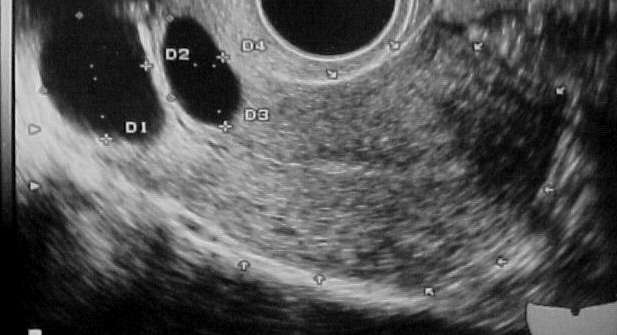

كيس المبيض عبارة عن ورم غير يتشكل في أي مرحلة عمرية لدى النساء، مشابه لكيس صغير مملوء بالسوائل، غالبا ما يكون حجمه أقل من 5 سم. ينقسم الكيس إلى نوعين: الكيس الوظيفي ويمثل 90 في المئة من حالات الأكياس المبيضية، ويرتبط بوجود خلل هورموني، هذا الكيس قد يختفي تلقائيا في غضون أشهر أو مع العلاج بالأدوية .

ـ الكيس العضوي نادراً ما يحدث، وهو يحتاج الى تدخل سريع لتجنب مضاعفاته الخطيرة. ويمكن الكشف عن كيس المبيض من خلال اعراض عدة وهي: وجود ألم في أسفل البطن، جس كتلة في البطن، اضطرابات في الدورة الشهرية، إمساك، ظهور حب الشباب، تكاثر شعر الجسم، مشكلة العقم.

كما يمكن الكشف عن وجود كيس المبيض بواسطة الموجات فوق الصوتية البسيطة، لدى طبيب النساء المختص. أما بالنسبة الى العلاجات فتختلف حسب طبيعة الكيس، وغالبا ما يصف الطبيب حبوب منع الحمل لمنع التبويض اثناء وجود كيس وظيفي، ومن الضروري متابعة طبية في الأشهر الموالية للتأكد من أن الكيس اختفى. وفي حال وجود الكيس العضوي المؤلم والكبير جدا، يجب إجراء عملية جراحية لتفادي المضاعفات كالتمزق والنزف.